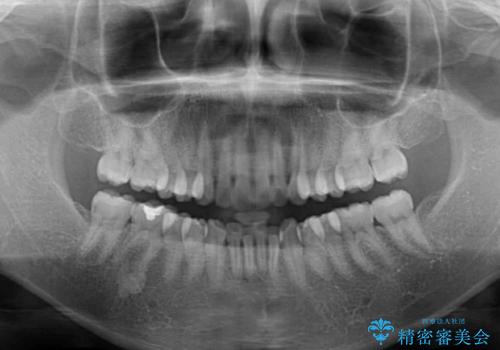

- 前歯のデコボコを気にして来院された患者様です。

当初は口元の突出感はあまり気にされていない様子だったので、インビザラインによる非抜歯矯正をお勧めしたが、ふっくらとした口元を改善したいとのことで、積極的に口元の突出感を改善することとしました。

上下左右第一小臼歯4本の抜歯を行い、ワイヤー装置による矯正治療を行うこととしました。